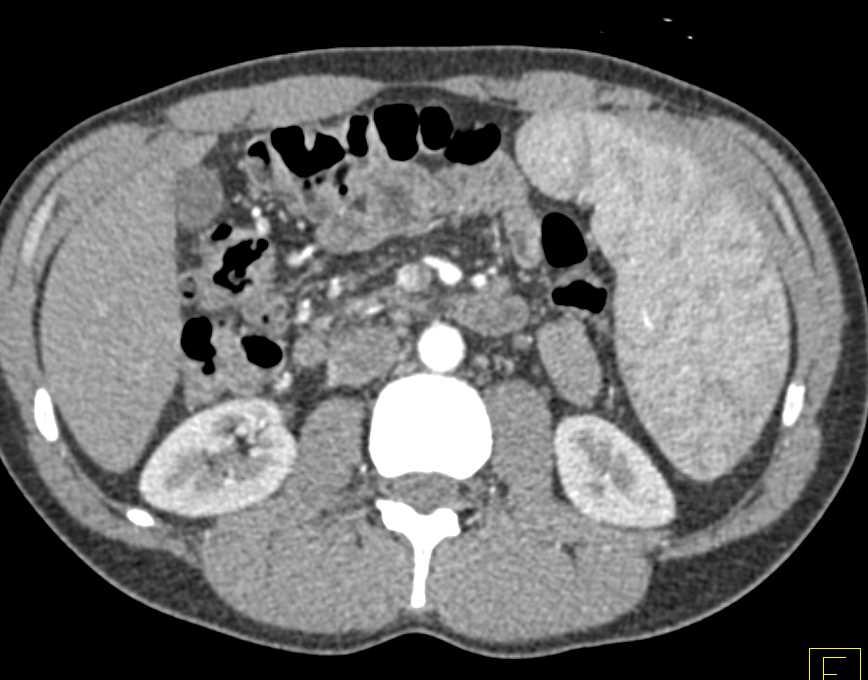

Cystic Splenic Hemangioma